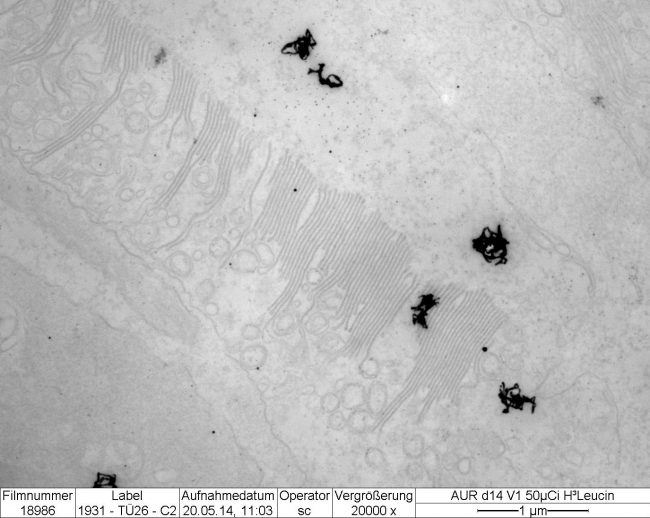

- Electron Microscope

- Electron Microscope